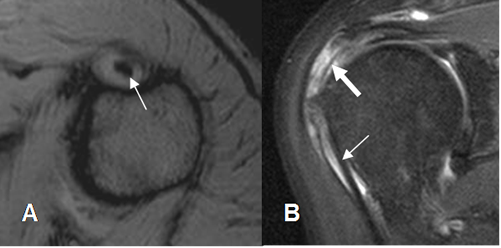

Fig 148. Tendinitis aguda de la cabeza larga del bíceps.

A: RM coronal en T1 y B: RM coronal en STIR. Tendón de la cabeza larga del biceps hiperintenso en T1 y STIR, por inflamación aguda.